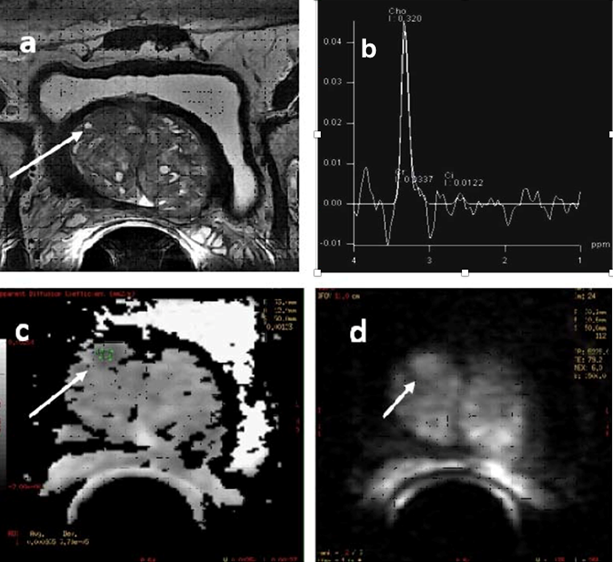

To Determine the Diagnostic Accuracy of Magnetic Resonance Spectroscopy (MRS) In Detection of Prostate Cancer in Patients with Prostatomegaly and Elevated PSA Levels, Taking Biopsy as Gold Standard

Dr. Rafay Gul, Dr. Hina Pathan, Dr. Jaideep Darira, Dr. Kashif Shazlee, Dr. Ashraf Amir Ali, Dr. Sara Zafar

International Journal of Innovative Research in Medical Science·February 2, 2022